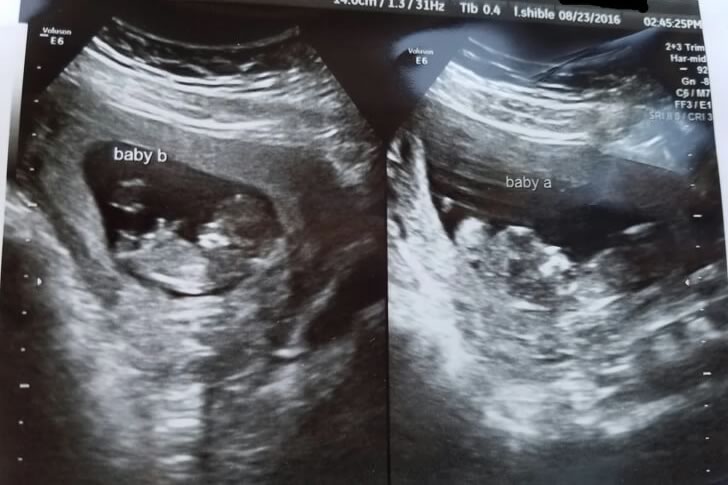

Lilly and Pradeep were filled with disbelief and excitement when the pregnancy test revealed not just one, but two babies on the way. For years, they had dreamed of becoming parents, and now that dream was coming true—twice over. Their hearts raced with joy, but in the background loomed the intimidating thought of raising twins. They knew their world was about to be flipped upside down.